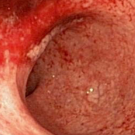

A 60-year-old man presented to the emergency department with abdominal pain, mild rectal bleeding, tenesmus, and frequent liquid mucous stools for 18 days, reporting “loose stools” in the morning and...